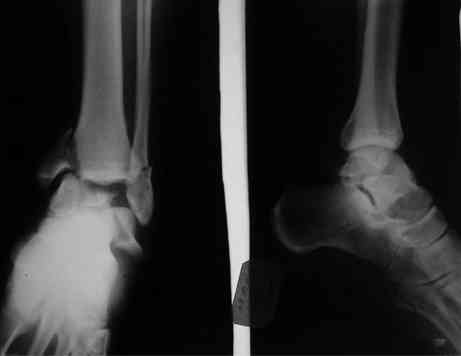

Interesting case

The ankle joint looks ruined. I wonder howcome is it as ruined after 2 days. I would open the joint( Some people would artroscope it) and judge the osteosynthes vs ankle fusion according to the ankle joint condition. The subtalar does not look injured, but if you feel there is a clinical

problem- CT it. Above all- when I see such an X-Ray I call the resident who ordered it and tell him that I would expect him first thing to reduce it on arrival since the soft tissue suffer and I hope that currently the p-nt is reduced to some extent at least.

Sorry- I revised it and the talus is fractured- take him to the theater at once and reduse it with Int Fix

The soft tissue will be a problem- Ex Fix will be better thn plaster

а основании двух видов ренгенограмм невозможно радикально решить о необходимости открытой репозиции или первичного артродеза.

Для оценки состояния нужны дополнительные исследования, например Canale или Broden ренгенограммы и Компьютерная томография.

При переломах тарана всегда имеется риск AVN, а классификация Hawkins поможет разобраться с предполагаемыми осложнениями.

Если в первом типе, когда перелом шейки без смещения, тогда AVN менее 10%, при втором типе когда имеется смещение и вывих тарана в субталарном сочленении меньше 40%, а при типе III когда смещение в голеностопном и субталарном суставах - около 90% и в типе IV, когда происходит полный вывих, риск AVN достигает 100%.